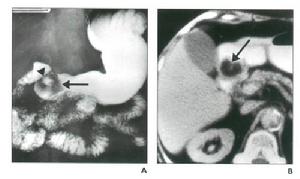

克隆氏病 有重要意義。胃腸道鋇餐造影,能了解克隆病末端迴腸或其他小腸的病變範圍,可見到節段性分布的特徵,病變偏腸系膜緣,小腸黏膜的皺襞增厚、低平或消失和卵石征。X線檢查可與腸結核鑑別,腸結核的刺激征較多見。鋇劑灌腸有助於結腸病變診斷,且常顯示末端迴腸黏膜增粗,結腸管腔狹窄並縮短;潰瘍間有炎性息肉樣充盈缺損,亦有出現瘺管和腸梗阻徵象者。氣鋇雙重造影,可提高小腸或結腸克隆病的診斷率。X線腹部平片,可見腸袢擴張和腸外塊影。

X線計算機體層攝像(CT)檢查:確定腹腔或盆腔膿腫形成及範圍。